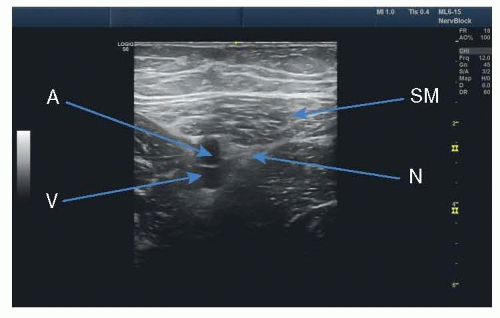

Using a high-frequency linear transducer, scan in a transverse orientation at the level of the inguinal crease. The femoral artery and femoral nerve should be easily identified in cross-section (FIG 1).

FIG 2 • Ultrasound image of adductor canal block. SN, saphenous nerve; SM, sartorius muscle; A, femoral artery; V, femoral vein.